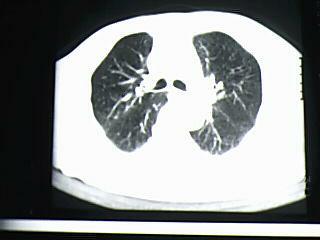

标题: CT19768:男 61岁 胸痛 咯血 一周。无发烧、无结核病史。 [打印本页]

标题: CT19768:男 61岁 胸痛 咯血 一周。无发烧、无结核病史。

右下肺支气管扩张

考虑 右下肺感染性病变,建议抗炎后复查。

考虑右肺下叶感染性病变;建议抗炎治疗后复查。

考虑右肺下叶感染性病变,建议抗炎治疗后复查。

右下肺感染性病变,建议抗炎后复查。支持